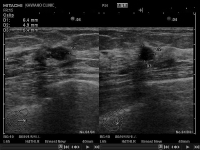

- 超音波検査

- 妊娠中の方の赤ちゃんを検査する方法とほぼ同じ方法で乳房の検査をします.ですから何度も繰り返し検査が可能です.乳房に超音波をあててその反射を画像にして「しこり」の性状をみて診断します.乳腺や甲状腺の超音波検査では体の表面に近いところを調べることのできる専用の装置が必要です。お腹を調べるための装置では精密な検査はできません。専用の装置であれば手で触れないような「しこり」の発見も可能です.また、マンモグラフィで異常が見つかりにくい若い方や乳腺の脂肪化の進んでいない方は超音波検査の併用がお勧めです。出来れば日本乳腺甲状腺超音波診断会議主催の乳房超音波講習会を受講された医師や技師が検査を行う施設で受けられる事をお勧めします(現在名簿などは公開されていませんが受講証が発行されています)。

- (画像をクリックすると拡大できます)